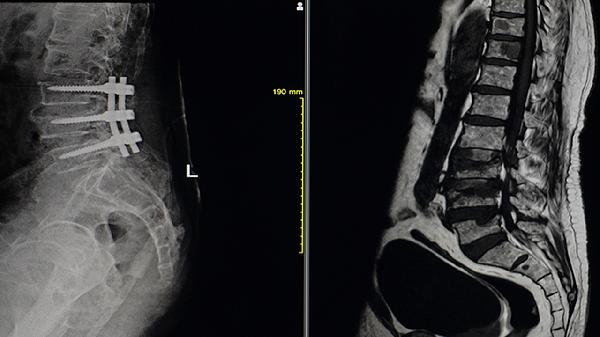

骨髓炎是指的感染微生物引起的骨骼炎症,临床上可以分为脊柱,骨髓炎以及四肢骨髓炎,脊柱骨髓炎,又叫做血缘性的骨髓炎,主要病因就是感冒,或者是其他部位骨关节的炎症,或者是脏器的炎症